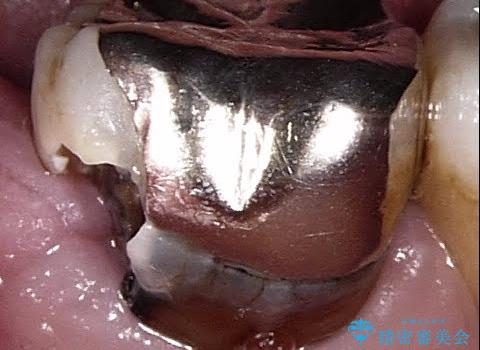

上顎の歯が全体的に前方に位置しているのと、前から2番目の歯が通常よりも小さい矮小歯という状態でした。

出っ歯をなおすために上顎の前から4番目の歯を抜歯して、引っ込めるのと、前から2番目の歯に通常の大きさのオールセラミックを装着して整った歯並びにすることにしました。